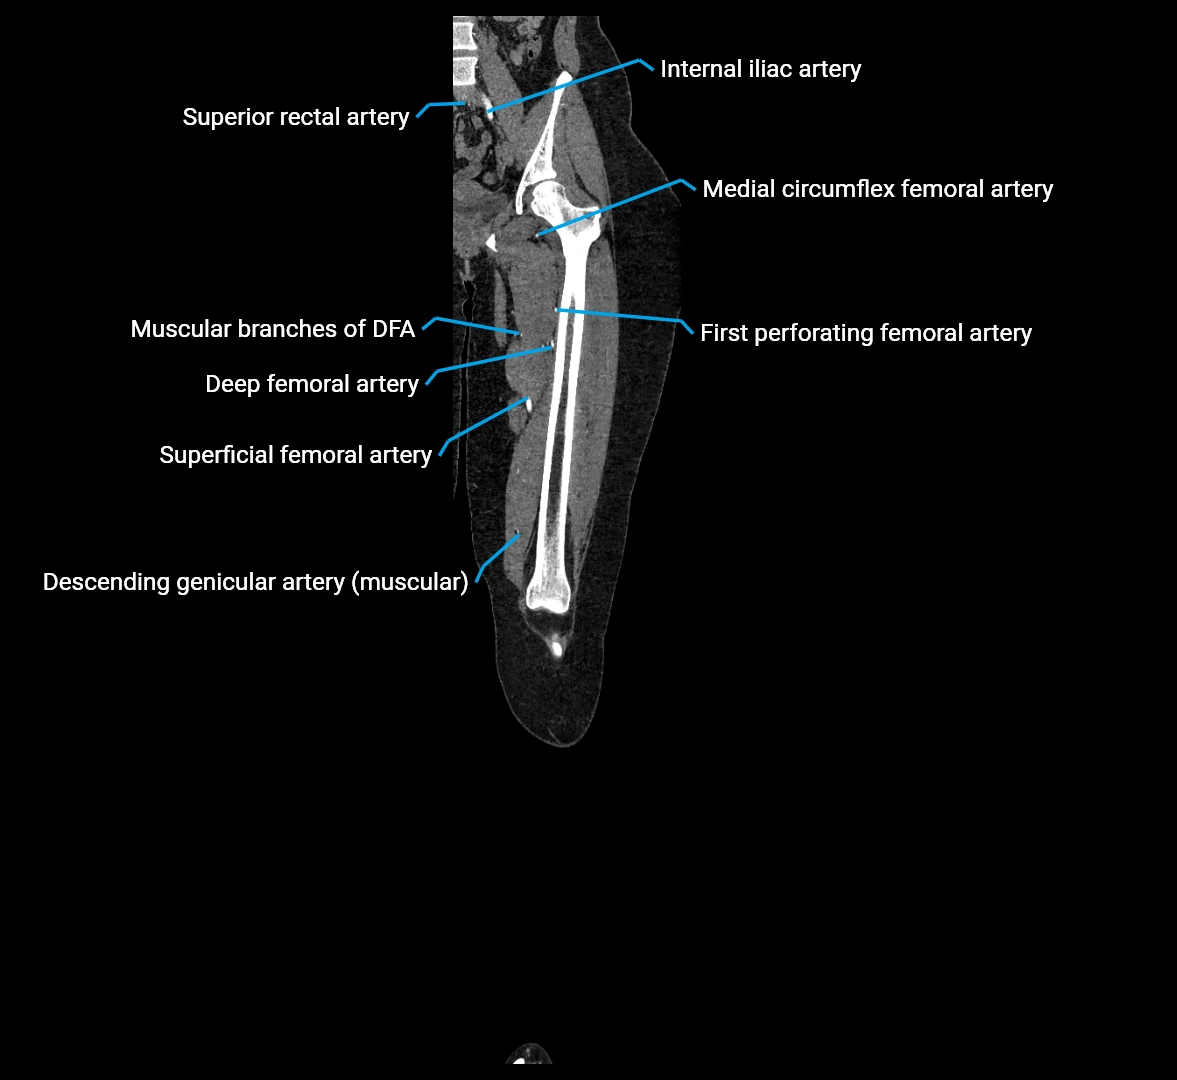

Contrast-enhanced CT (CTA):

• Gold standard for abdominal aortic imaging

• Provides excellent detail of lumen, wall, aneurysm, thrombus, and branch vessels

• Multiplanar and 3D reconstructions help in aneurysm measurement, stent graft planning, and dissection evaluation